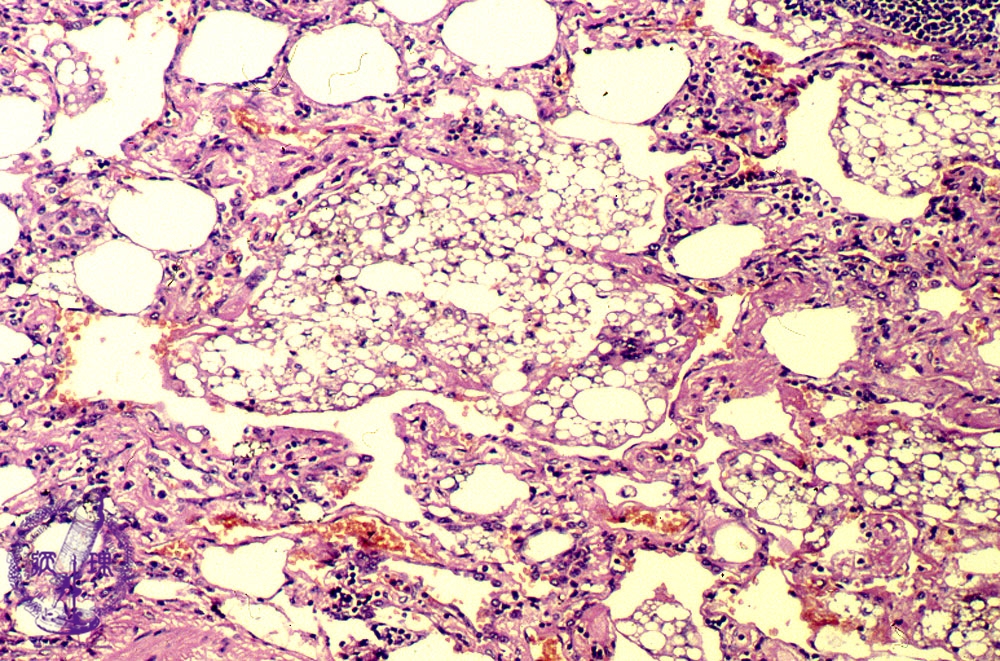

- (14)Lipoid pneumonia

Microscopic view (HE stain, Middle-power-view): Lipid and cholesterol crystal laden macrophages are seen within alveoli and alveolar septa accompanied by an inflammatory cell infiltrate.